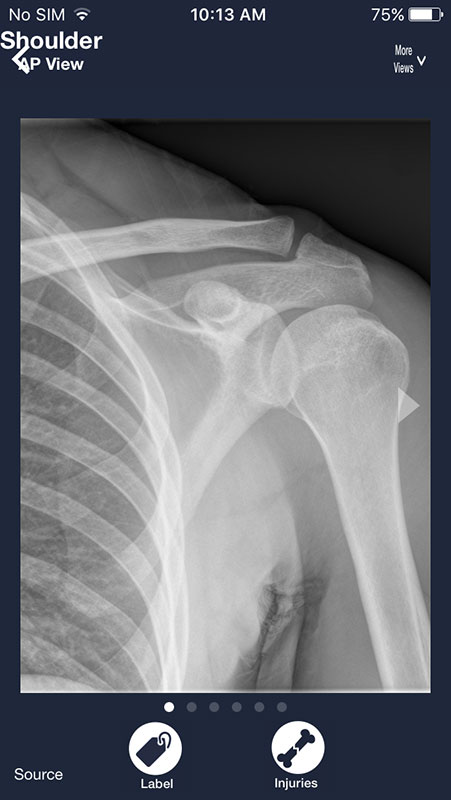

Tapping on any of these sections opens a series of images featuring a selected body part. For example, if you've chosen shoulder, you'd be presented with an X-ray image of a shoulder.

You can swipe the screen to navigate through the series of images. Each following image is annotated and contains a piece of advice on what to look for on a radiograph in order to distinguish between normal anatomy and abnormalities/pathologies.